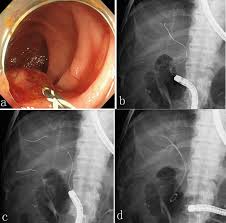

Ce Clinical Endoscopy Clin Endosc 2234 2400 2234 2443 Korean Society Of Gastrointestinal Endoscopy 10 5946 Ce 2019 032 Ce 2019 032 Case Report A Rare Fatal Bile Peritonitis After Malposition Of Endoscopic Ultrasound Guided 5 Fr Naso - Used for endoscopic stent placement to drain obstructed biliary ducts.

A Double Guidewire Technique To Facilitate Deep Cannulation And Stenting In A Patient With Altered Gastrointestinal Anatomy Kawabata Journal Of Medical Cases - Stent patency in malignant lower biliary obstruction with chemotherapy.